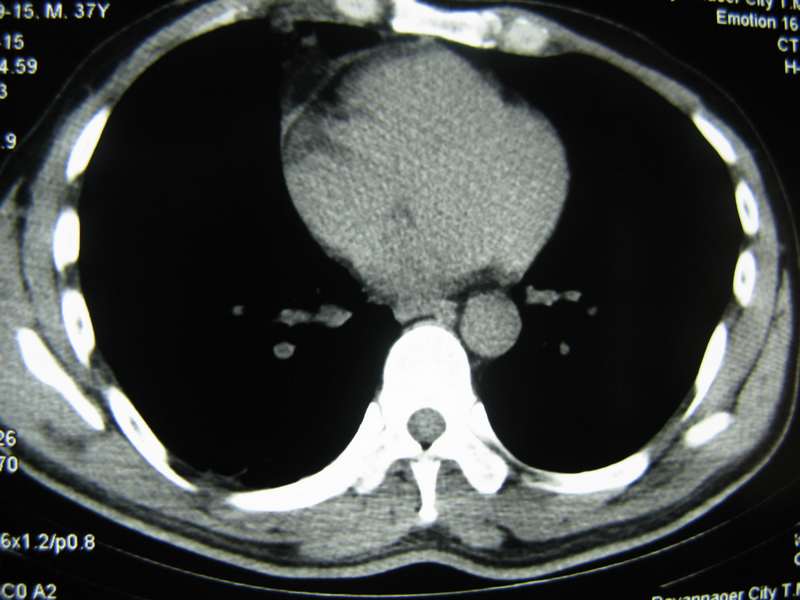

男,37岁,主述胸疼厉害,无咳嗽,无发热,血象也不高,病灶内ct值脂肪密度,右侧胸腔内少量积液,同道们考虑什么?谢谢!

脂肪垫,右下肺感染,少许积液是症状所在

纵膈脂肪堆积,右肺慢性炎症。

两肺下叶基底段纤维灶,右肺下叶基底背侧相应胸膜肥厚,右肺中叶内侧段部分不张。前中下纵隔团块状脂肪影,随访除外胸腺脂肪瘤。

纵膈脂肪堆积,右肺慢性炎症

脂肪垫;右肺慢性炎症。